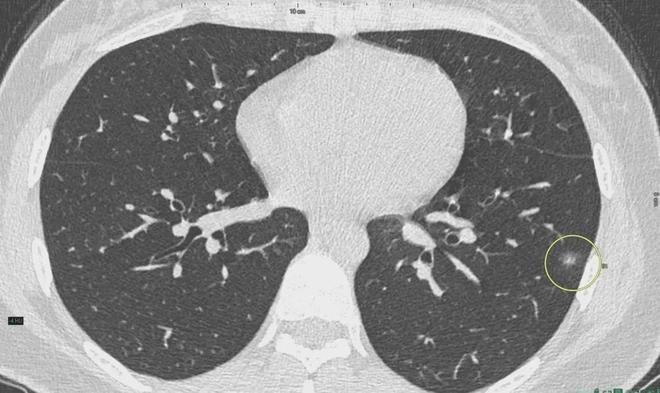

6、定期體檢:定期進行肺部檢查,及時發(fā)現(xiàn)并治療肺結(jié)節(jié)。